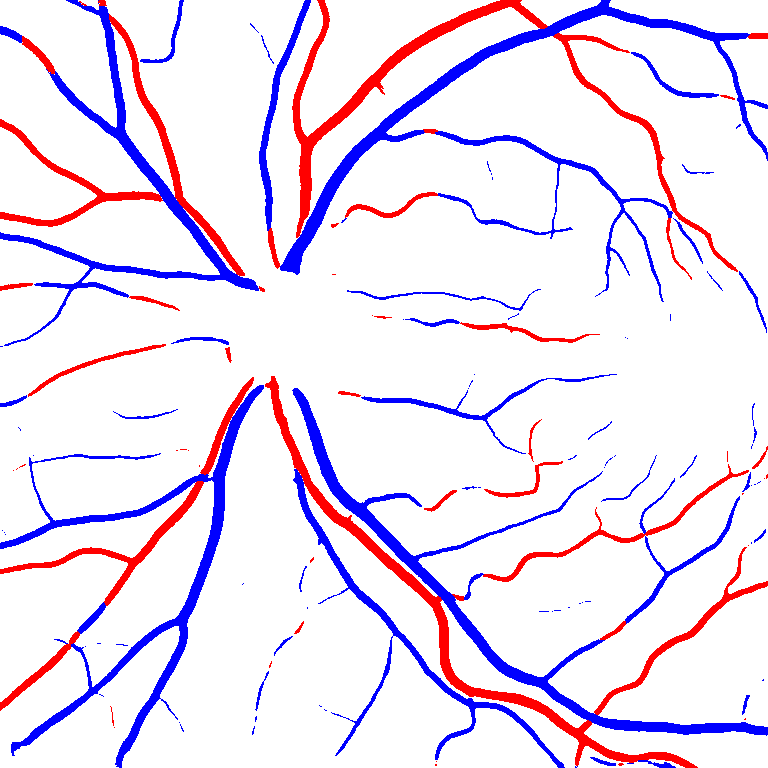

As reported in Table IV, we compared the SegRAVIR model against competing deep learning-based segmentation approaches on the RAVIR dataset. Evidently, SegRAVIR outperforms these methods as judged by all metrics for artery and vein classes with a healthy margin. In terms of Dice score, SegRAVIR outperforms CE-NET, IterNet and AG-Net by , and for artery segmentation and by , and for vein segmentation, respectively. Fig. 4 presents a qualitative comparison of the semantic segmentation outputs of SegRAVIR, CE-Net, and U-Net. Specifically, SegRAVIR yields more accurate vessel topology (i.e., thickness and orientation) segmentation with higher pixel-wise classification accuracy.

(a) (b) (c) (d) (e) (f)